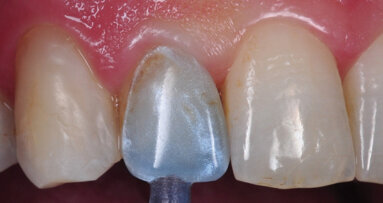

S’il manque à la dent nécessitant une restauration une crête marginale, ou les deux, et si ces zones ont été restaurées auparavant ou le seront, la mise en place d’un composite collé ne sera pas une restauration définitive satisfaisante (Fig. 10). Les crêtes marginales confèrent une résistance à la flexion cuspidienne de la dent et augmentent sa solidité. Lorsque les crêtes sont absentes, la flexion cuspidienne est accrue sous la charge fonctionnelle de la dent et par conséquent le risque de fracture lors de la fonction masticatoire l’est également.

La restauration de ces dents nécessite une reconstitution corono-radiculaire, éventuellement associée à des clavettes ou d’autres éléments de rétention du moignon coronaire, suivie de la pose d’une couronne de recouvrement total. Souvent, des tenons ne sont pas nécessaires car la structure dentaire résiduelle, au niveau des cuspides après préparation de la couronne, est suffisante pour maintenir le moignon coronaire et il est possible de réaliser une ferrule. Un tenon peut être envisagé chez les patients souffrant de bruxisme ou serrant les dents de façon anormale, ou chez les patients présentant une occlusion susceptible de soumettre la dent restaurée à des charges plus importantes, en raison de sa position par rapport au plan occlusal. Lorsqu’une ferrule adéquate ne peut être réalisée, le praticien devrait envisager un allongement coronaire chirurgical par résection osseuse ou égression orthodontique, afin d’en faciliter l’obtention.